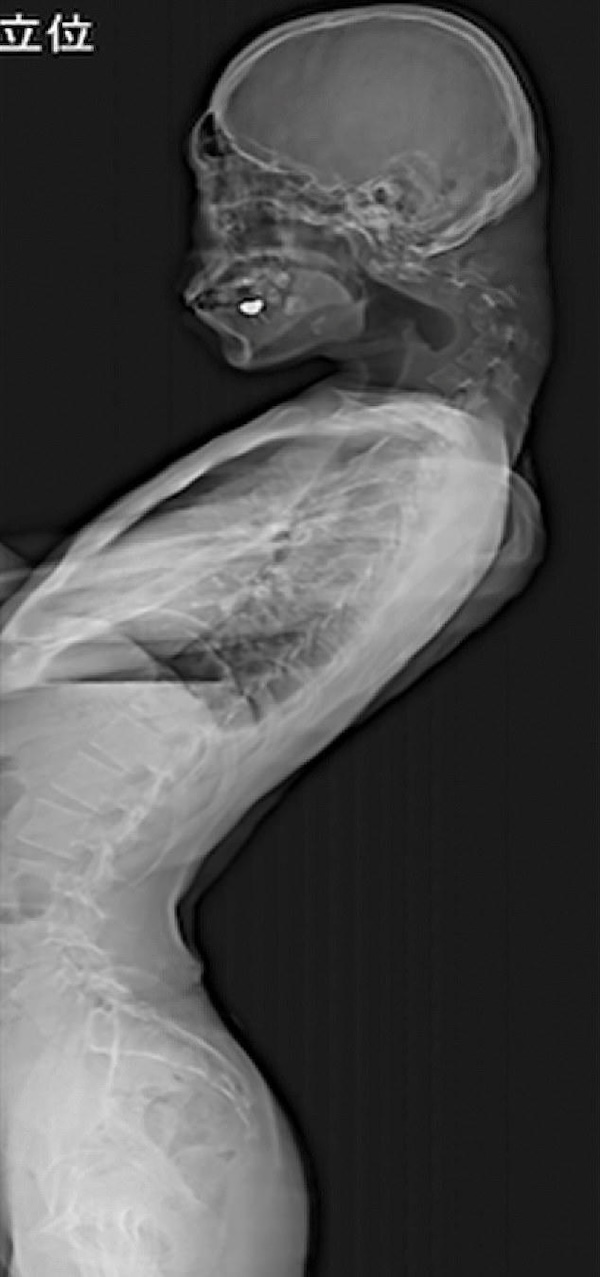

25-Year-Old Develops Permanent Neck Bend From Staring at His Phone

Once an active child, his social life took a nosedive due to bullying during his teenage years.

Retreating into the digital realm, hours of gaming and scrolling soon turned into years, all the while his neck bending further and further towards the screen.

This prolonged posture didn’t just earn him high scores. He developed a pronounced bulge at the back of his neck, rendering him unable to lift his head, and was diagnosed with Dropped Head Syndrome.